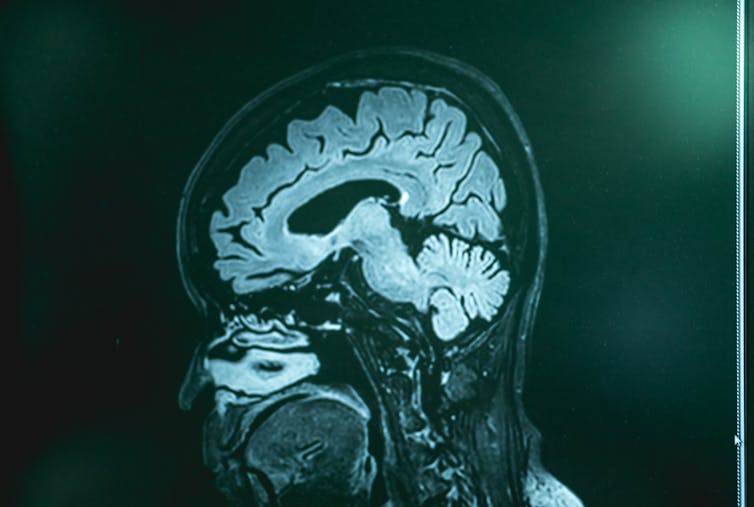

This variant was given its name because most of the tissue loss occurs in the right temporal lobe of the brain. This brain area is mainly involved in understanding concepts and deriving meaning from nonverbal information, such as social cues. Scans of CP’s brain showed that large portions of this region were missing.